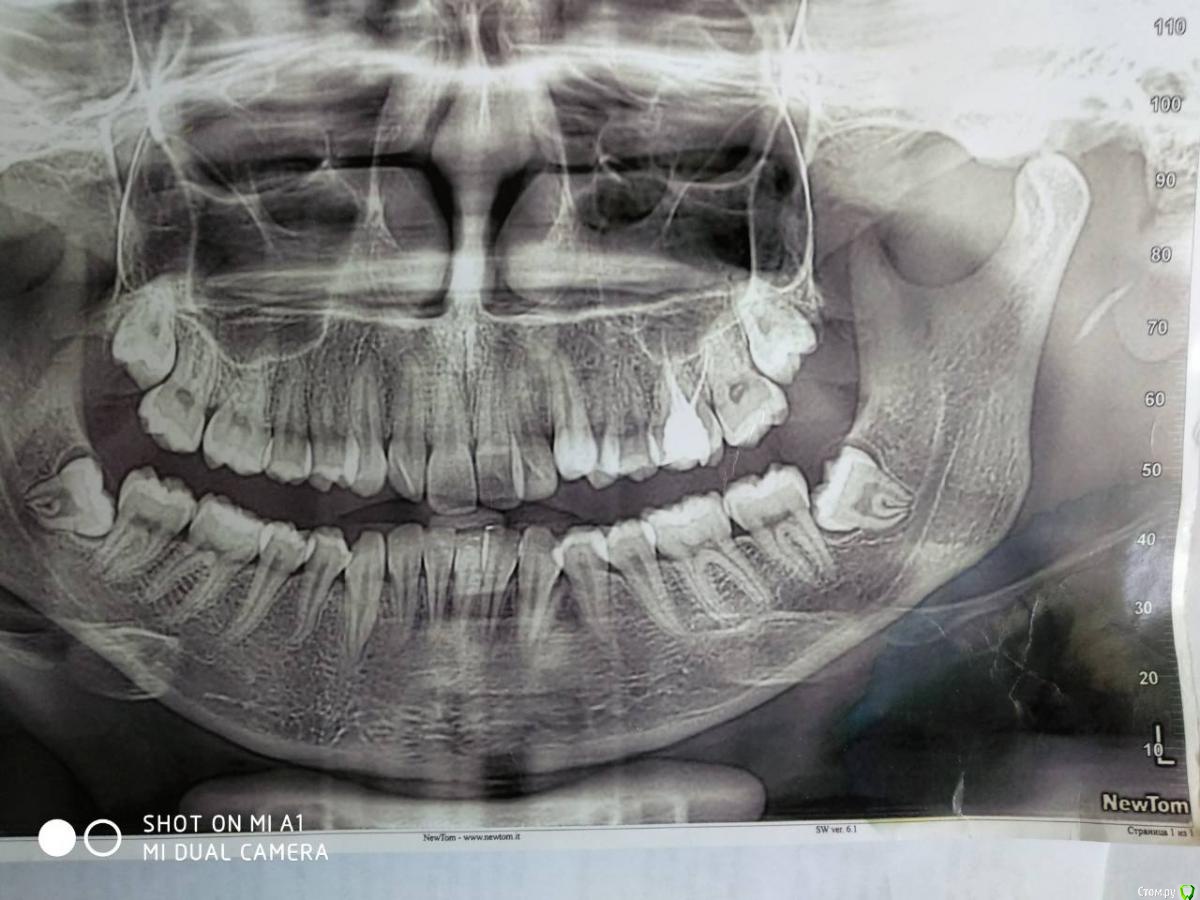

Monkey Опубликовано 20 апреля, 2018 Поделиться Опубликовано 20 апреля, 2018 Возможно ли ортодонтическое лечение без удаления зубов или с минимальным удалением (можно ли ограничиться только нижними восмерками)? Если лечение будет проводиться без удаления премоляров (а удалять их крайне нежелательно), то удаление верхних и нижних зубов мудрости необходимо. Ссылка на комментарий

Гелла Опубликовано 23 апреля, 2018 Автор Поделиться Опубликовано 23 апреля, 2018 Здравствуйте, спасибо за ответ.Сейчас удаляем нижние зубы мудрости. Верхние зубы мудрости непосредственно "входят" в гайморовы пазухи, для их удаления требуется сложная челюстно-лицевая операция с ушиванием(?) ходов в гайморовы пазухи.Кроме того, все ортодонты, которые консультирование, настаивали на удалении как минимум двух верхних "четверок".Как, по Вашему мнению, стоит ли сохранение "четверо" столь сложной и малопрогнозируемой операции? Ссылка на комментарий

Monkey Опубликовано 23 апреля, 2018 Поделиться Опубликовано 23 апреля, 2018 Здравствуйте, спасибо за ответ.Сейчас удаляем нижние зубы мудрости. Верхние зубы мудрости непосредственно "входят" в гайморовы пазухи, для их удаления требуется сложная челюстно-лицевая операция с ушиванием(?) ходов в гайморовы пазухи.Кроме того, все ортодонты, которые консультирование, настаивали на удалении как минимум двух верхних "четверок".Как, по Вашему мнению, стоит ли сохранение "четверо" столь сложной и малопрогнозируемой операции?Если не хотите в будущем получить проблемы с височно-нижнечелюстным суставом, то, однозначно, стоит. Главное найти грамотного хирурга. Ссылка на комментарий